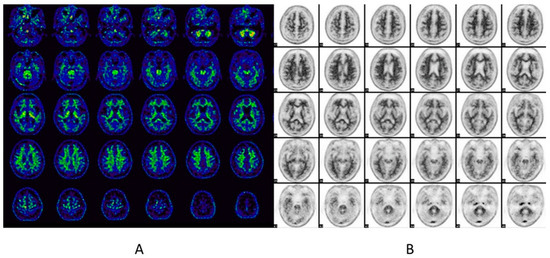

6.1.1. Imaging Data Display [45,50]

|

| FDG PET |